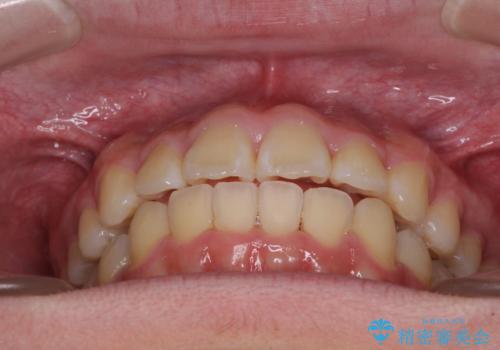

中学生と言うこともあり、1年強の短期間で終了しました。

歯磨きがしっかりとできないと虫歯になるリスクがありましたが、治療期間中は清潔な状態を保っていただけました。